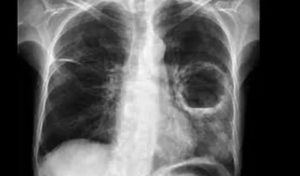

А вот для определения очистившейся формы легочного абсцесса следует обратить внимание на следующие моменты:

- стенки капсулы становятся намного тоньше;

- отсутствует уровень жидкости;

- происходит зарастание стенок полости с помощью соединительной ткани, это способствует тому, что очистившийся абсцесс ещё какое-то время остаётся в первичном размере, а затем заменяется рубцом.

В результате этого можно отметить, что при отсутствии различного рода осложнений абсцесс легкого и, соответственно, его рентгенограмма проходят три основных стадии:

- Первичная (острая).

- Вторичная (хроническая).

- Ложная (очистившийся абсцесс).

Острая стадия длится приблизительно 3 месяца, а хроническая — до полутора месяцев.

Абсцесс образуется в легких из-за гнойного расплавления легочной ткани, спровоцированного гнойной или аспирационной пневмонией, инфарктом легкого, распадом раковой опухоли, септикопиемией и рядом других факторов. Абсцесс легкого на рентгенограмме выглядит по-разному в зависимости от стадии и состояния запущенности процесса.

Форма воспаления легочной ткани на рентгеновских снимках зависит от следующих факторов:

Абсцесс легкого на рентгенограмме

- в острой – правильная форма с нечеткими контурами;

- в хронической – неправильная форма с множественными «карманами».

- Размер гнойно-деструктивного процесса:

- небольшой – не меньше 2 см в поперечнике;

- большой – более 10 см в поперечнике.

- однородная – до прорыва в бронх;

- резко неоднородная – после прорыва с визуализацией просветления и горизонтальным уровнем из-за появления газа и жидкости в полости.